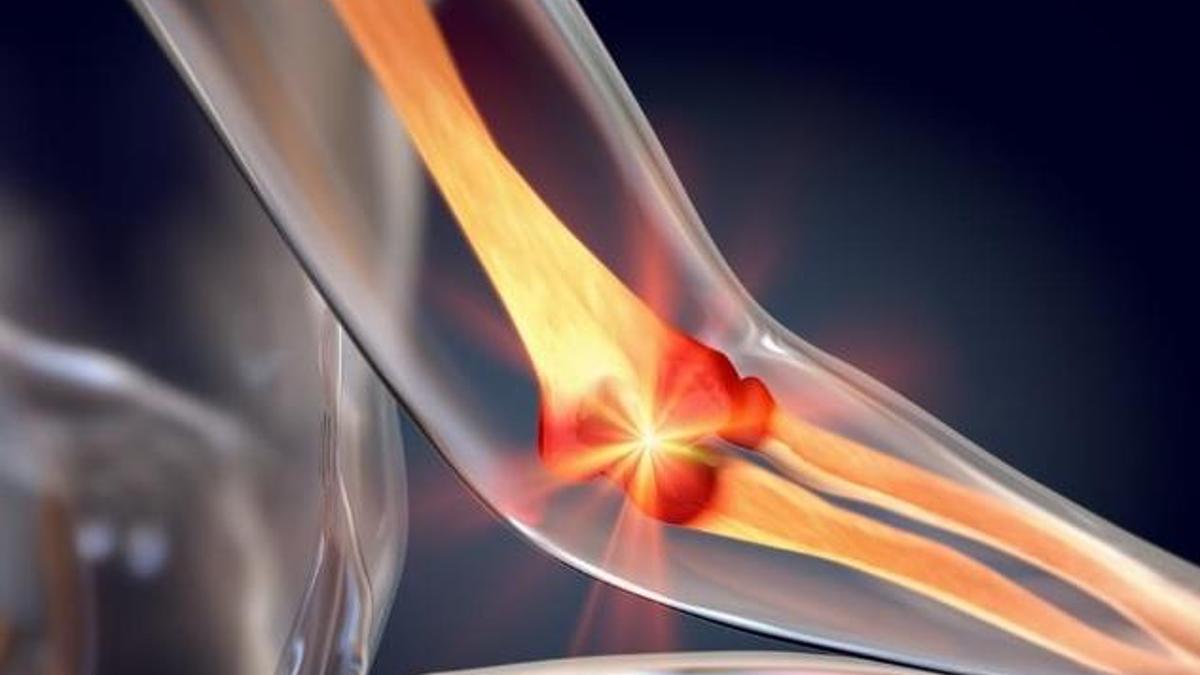

Futbol gıda veya takviyeden alınır. Kaslar, kemikler, dişler, kan pıhtılaşması ve metabolizma üzerinde büyük bir etkiye sahiptir. Vücudun farklı nedenlerle kalsiyum almasından sonra bazı hastalıklar ortaya çıkabilir. Kalsiyum eksikliğinde kemik reabsorpsiyonu, rasortizm, osteomalasya gibi hastalıklar meydana gelebilir. Aynı zamanda, bu mineralin olmaması depresyona yol açabilir.

Birçok insan futbol eksikliğini deneyebilir. Futbol esas olarak kemiklerde ve dişlerde korunur. Bu nedenle, kalsiyum eksikliği meydana geldiğinde, kemikler ve dişler ilgilenmeye başlar. Futbol eksikliğine neden olabilecek bazı durumlar var.